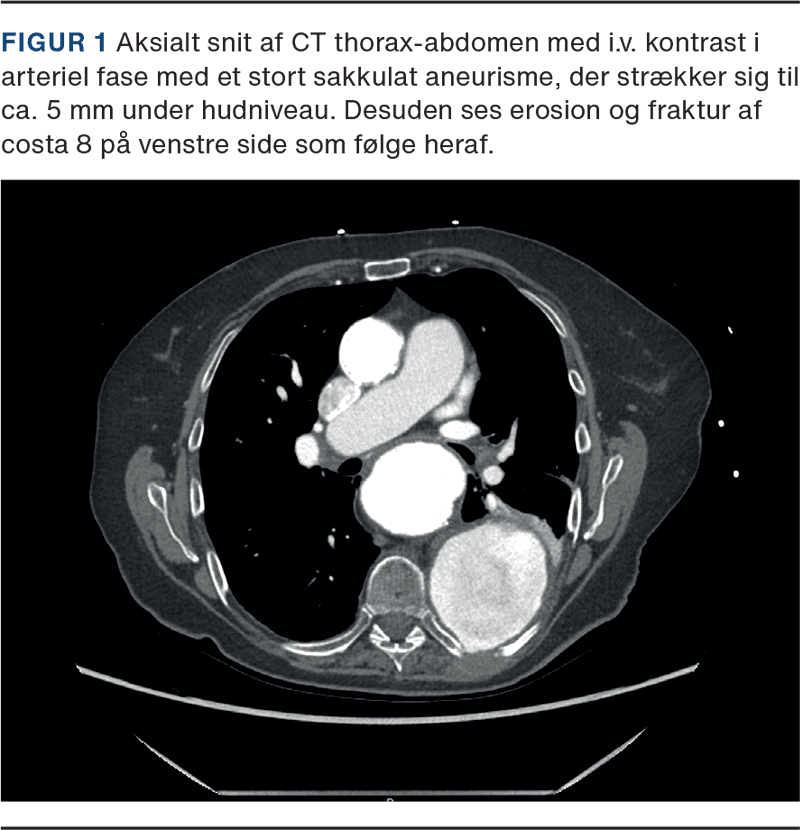

CT viste imidlertid ingen tegn på ruptur, men derimod fraktur og diastase posteriort i venstre costa 8 i relation til det torakale aortaaneurisme, der var tiltaget med 1 cm til nu 11,5 cm over 5 mdr. (Figur 1).

This case report presents an 82-year-old woman who presented with acute thoracic pain and back pain. The CT angiography excluded rupture but showed a progressing penetrating aortic ulcer with adjacent rib fracture and diastasis as the cause of the patient’s pain.